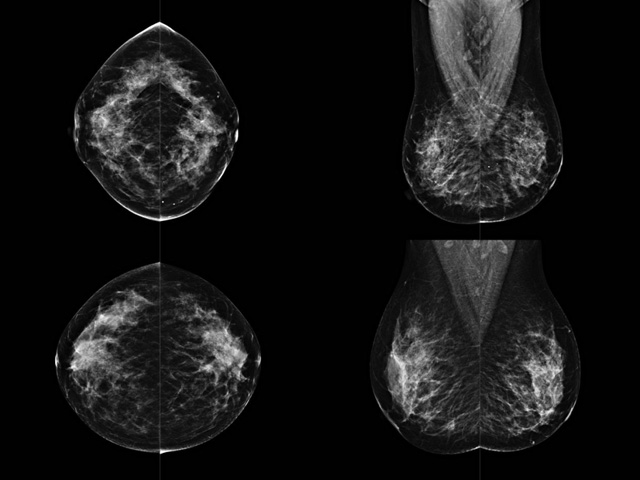

乳房檢查時候要注意一些細(xì)節(jié),需要更深入的了解這樣才能使檢查更準(zhǔn)確。乳腺DR是乳腺癌的篩查診斷工具設(shè)備。是乳房方面檢查的重要影像方法。它可以臨床檢查出早期的乳腺癌??梢耘袛嗔夹詯盒浴R驗樗梢詸z查出早期的病變。對良性惡性檢查的準(zhǔn)確率達(dá)到90%以上。發(fā)病高峰年齡為45歲到54歲。50歲檢查出來乳腺癌病患,可以讓死亡率下降3成。所以30-40歲女性每年做一次乳腺DR檢查。40歲以上就一年兩次。如果家族史有乳腺癌的30歲以下也需要做檢查。清晰顯示乳腺各層組織嚴(yán)重的乳腺增生,乳腺炎,乳腺外傷也建議1年檢查一次。極大提高了早期乳腺癌的敏感度和診斷率。

大角度、高質(zhì)量的乳腺檢查,可以讓女性帶來身體健康安全。為醫(yī)生提供了高清影像數(shù)據(jù)。乳腺檢查時候各個部位影像顯示出來。白色乳腺導(dǎo)管跟纖維結(jié)締組織。模糊的是脂肪。病變一般是不透明的白色。有需要放大來檢查。乳腺DR沒有重疊偽影。輻射劑量更少。因為乳腺癌發(fā)病每年都有所提高,對女性都造成了嚴(yán)重的身體健康危害。早做檢查早治療是不可忽視的舉措??梢源蟠蟮慕档?/span>死亡率。保證身體健康。一般檢查避開經(jīng)期,來完7天左右是最佳的檢查時間。絕經(jīng)的女性就沒有要求。孕婦不參加乳腺DR檢查, 6個月內(nèi)準(zhǔn)備妊娠的婦女也不宜行此檢查。